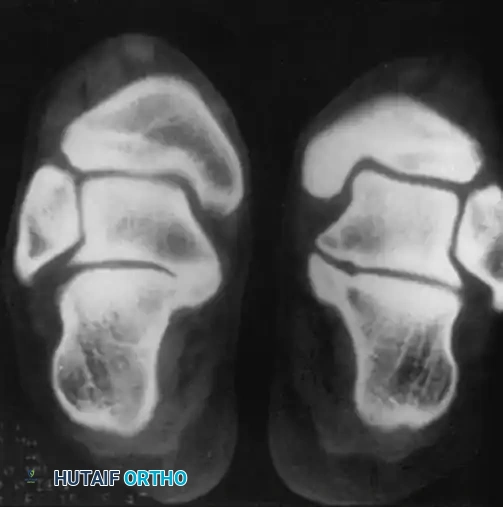

Determining the exact type and location of the tarsal coalition is critical for preoperative planning. Computed Tomography (CT) is the gold standard imaging modality for this purpose, providing high-resolution multiplanar views of the complex hindfoot articulations.

FIGURE 89-31: CT scan demonstrating a medial facet tarsal coalition of the calcaneus and talus in a young patient presenting with frequent ankle sprains.